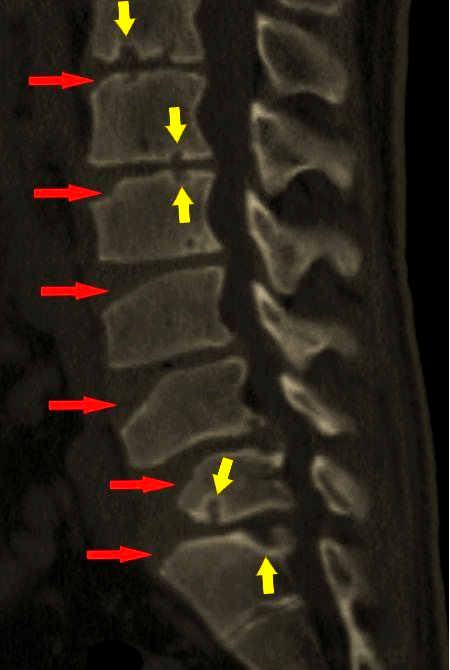

休门氏病ct图片

休门氏病(青少年驼背最常见病因)的影像表现与临床

中间图符合腰型休门氏病标准.右图符合典型休门氏病标准.